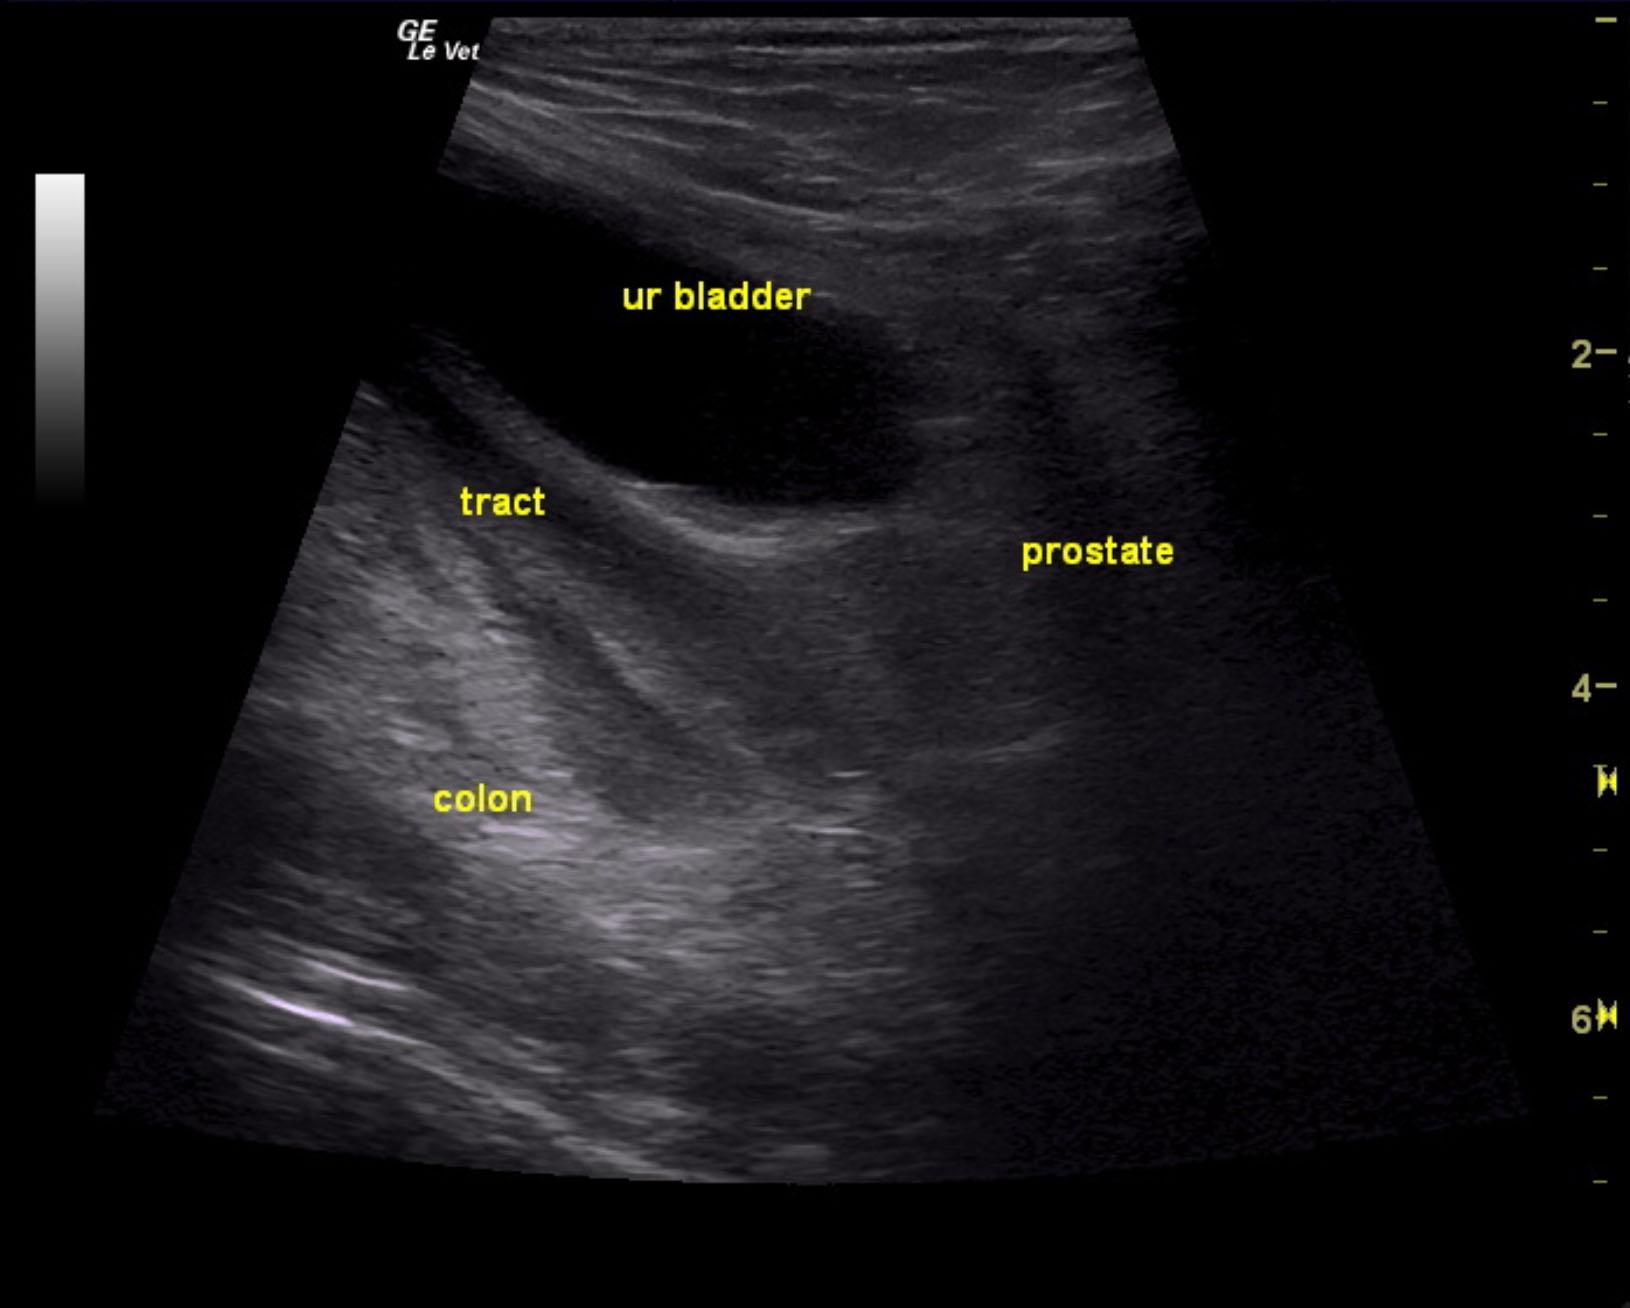

The urinary bladder itself presented minor thickening and minor debris. A tubular structure was noted in a position between the colon and the urinary bladder with dilation.

Purulent material was obtained on ultrasound-guided centesis without complications. However, reactive mesentery was noted throughout the pelvis. The position of this tube would fit with a uterus. This patient may be a hermaphrodite with secondary pyometra. I cannot make a direct connection from the tubular structure to the prostate itself as they appear to be separate. I recommend exploratory surgery with removal of this structure. The ureters do not appear to be involved. The position and structure would be that of a uterus. Therefore, treatment for pancreatitis and localized infection in the region of the pelvis would be recommended with IV fluid support, broad spectrum antibiotics such as Enrofloxacin and Clindamycin combination as well as exploratory surgery. If the tubular structure is confirmed to be a uterus and hermaphroditism then examination for possible ovaries would also be warranted even though none were visible in the image set. Regardless, this tubular structure necessitates surgical resection.

Tubular structure in the pelvis region.